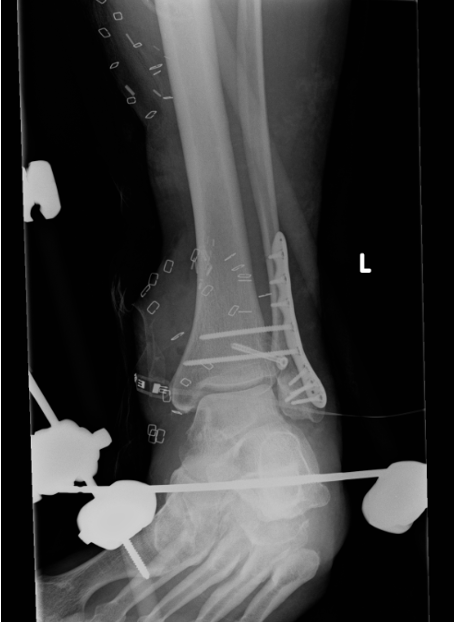

ORIF

Technique

Locking plates

Multiple syndesmotic screws